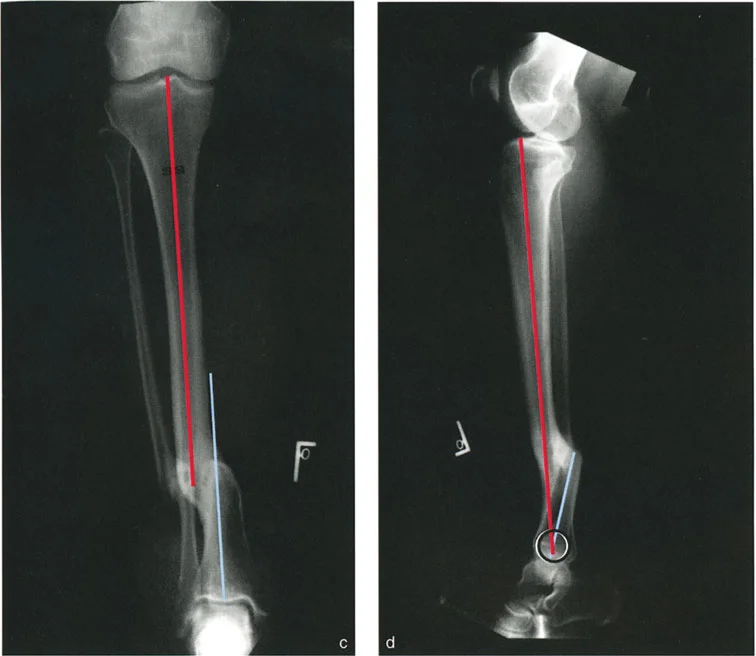

تشوهات المستوى التشريحي بزاوية 90 درجة

في هذا النوع، يكون الانحراف في مستوى تشريحي واحد (مثل المستوى الأمامي الخلفي)، بينما يكون الانزياح في المستوى التشريحي الآخر العمودي عليه (مثل المستوى الجانبي). لا يوجد انزياح في مستوى الانحراف، ولا يوجد انحراف في مستوى الانزياح. يكون مركز دوران الانحراف (CORA) عند مستوى الكسر.

مثال: التئام خاطئ في عظم الساق الأيسر حيث يوجد انحراف في المستوى الأمامي (الواجهة الأمامية) وانزياح في المستوى السهمي (الجانبي). لا يوجد انزياح في المستوى الأمامي ولا انحراف في المستوى السهمي.

التصوير الشعاعي بالأشعة السينية

تُعد الأشعة السينية (X-rays) الأداة الأساسية لتشخيص تشوهات العظام. يتم أخذ صور متعددة للطرف المصاب من زوايا مختلفة (الأمامية الخلفية، الجانبية، والمائلة) لتقييم التشوه في جميع المستويات. الأستاذ الدكتور محمد هطيف يولي اهتمامًا خاصًا لجودة هذه الصور ودقتها، حيث إنها الأساس الذي يُبنى عليه التحليل البيوميكانيكي.

تحليل CORA لتحديد مركز الدوران الفعلي

يُعد تحليل مركز دوران الانحراف (CORA - Center of Rotation of Angulation) حجر الزاوية في التخطيط الجراحي لتصحيح تشوهات العظام. يتطلب هذا التحليل فهمًا عميقًا للبيوميكانيكا العظمية وخبرة كبيرة، وهو ما يتميز به الأستاذ الدكتور محمد هطيف.

- ما هو CORA؟ هو النقطة الافتراضية التي يدور حولها الجزء البعيد من العظم بالنسبة للجزء القريب لتصحيح الانحراف.

- كيف يتم تحديده؟ يتم تحديد CORA برسم خطوط محورية على الأشعة السينية (AP و LAT) لكل جزء من العظم المشوه (القريب والبعيد). نقطة تقاطع هذه الخطوط هي CORA.

- أهميته: تحديد CORA بدقة يُمكّن الجراح من تخطيط قطع العظم (Osteotomy) في الموقع الأمثل. إذا تم إجراء قطع العظم عند مستوى CORA، يمكن تصحيح الانحراف بحركة زاويّة واحدة دون إحداث انزياح جديد أو زيادة الانزياح الموجود. هذا يقلل من تعقيد الجراحة ويحسن النتائج الوظيفية.